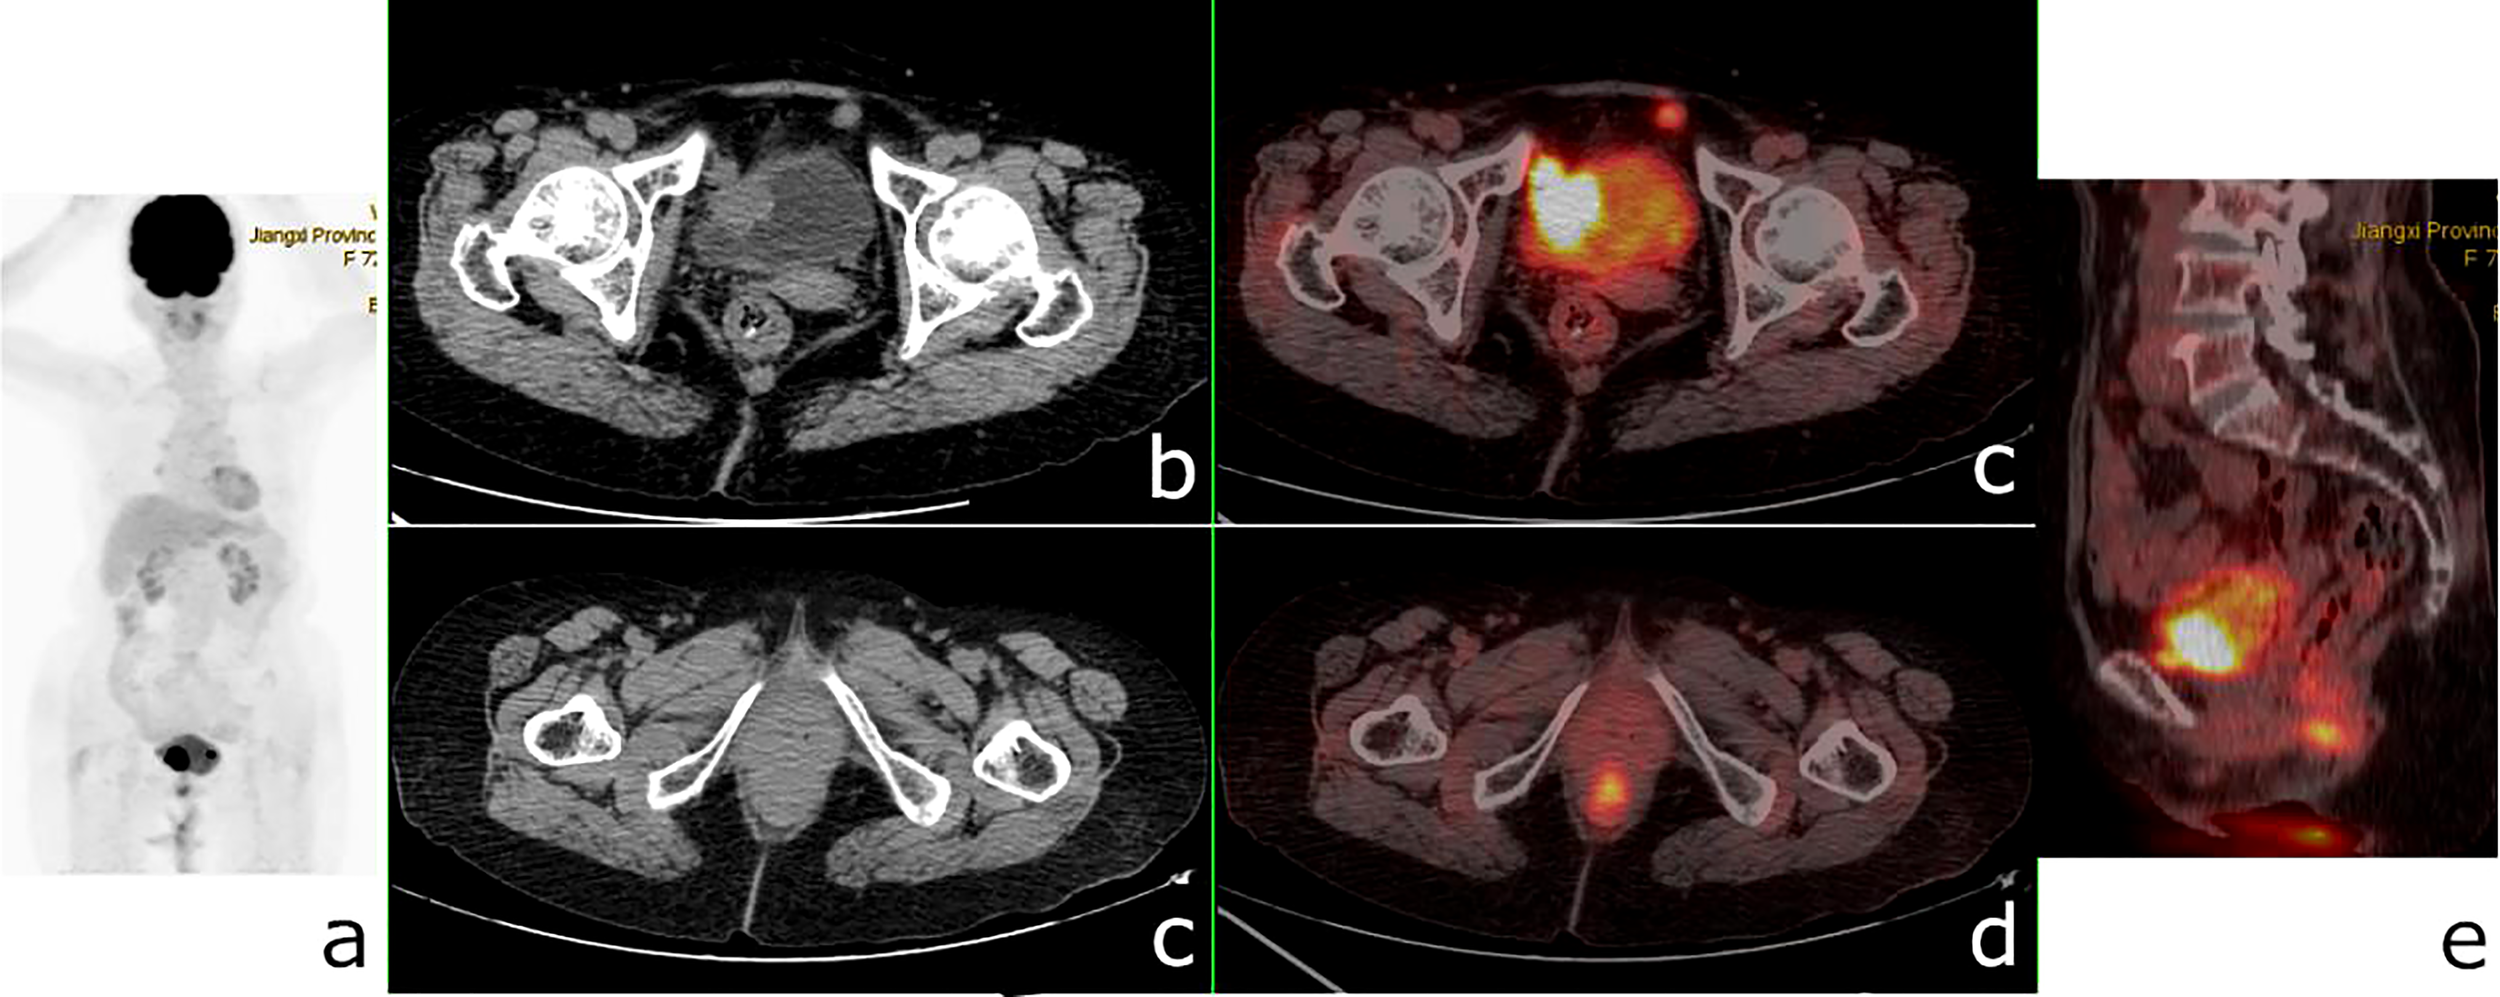

Figure 8 18F-fluorodeoxyglucose positron emission tomography/computed tomography (18F-FDG PET/CT) of a 72-year-old woman with bladder cancer and anal canal adenocarcinoma. PET/CT revealed a 26 × 24-mm nodule in the bladder wall with a maximum standardized uptake value (SUVmax) of 23.9, a nodular hypermetabolic lesion (SUVmax = 11.3) misinterpreted as physiological FDG uptake in the anal canal, and a small nodule with a diameter of 1 cm in front of the bladder (SUVmax = 8.9). (A) PET/MIP. (B, C) Axial CT. (C, D) Fusion images. (E) Sagittal fusion image.

FIGURE 9

To our knowledge, there are only a few studies evaluating the diagnostic performance of 18F-FDG PET/CT for SMPMNS. In this series, SMPMNS were considered in 28 cases, and most of the primary lesions (including diagnosed and misdiagnosed) have been revealed on 18F-FDG PET/CT imaging. We noted one primary tumor of SMPMNS that was more frequently missed on CI primarily due to the regional imaging modalities and the general lack of awareness regarding SMPMNS on the part of clinicians, with their attention tending to be focused on the identified primary lesion. 18F-FDG PET/CT, which can more comprehensively reveal lesions due to its whole body surveillance, will help in increasing clinicians’ awareness regarding SMPMNS. Additionally, one primary tumor of SMPMNS was easily mistaken for metastasis, especially in patients with metastases, which will more likely lead to confusion in the diagnosis. 18F-FDG PET/CT, which allows combining metabolic information with anatomic details, reduces the incidences of misdiagnosis, i.e., tumors with different clonal origins that were generally believed to have a different biological behavior, leading to different uptakes of FDG. Misinterpretation of a high FDG uptake in lesions as physiological uptake on PET/CT is also an important reason for the missed diagnosis (Figures 8, 9).